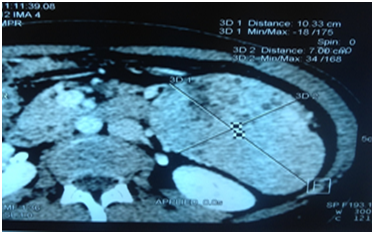

The clinical examination revealed a size 145cm (-3 SD/M.SEMPE) with a total impuberism. The hormonal tests showed a hypergonadotropic hypogonadism. The abdominal CT scan revealed a left hemi-abdominal mass with a large vascular pedicle (supernumerary spleen?) Figure 1. Our patient was followed for cardiac heart failure. The echocardiographic exploration found a left systolic ventricular dysfunction with a septum akinesia and an anterior wall hypokinesia. The left ventricular ejection fraction was 40%. It was therefore a dilated left ventricular non-compaction cardiomyopathy (Figure 2).

Figure 1 Abdominal CT scan: left hemi-abdominal mass with a voluminous vascular pedicle (supernumerary spleen?).